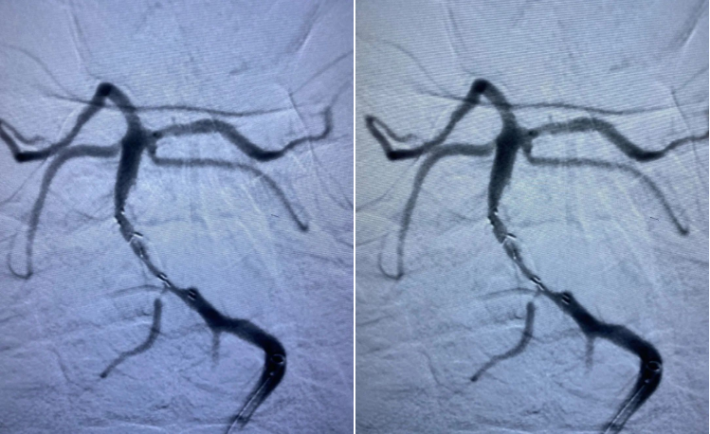

Solitaire AB 4mmx20mm成功挂住Enterprise 2。

尝试回收支架至5F Navien,牵扯力量比较大,提心吊胆。

经反复收拉尝试,最终取出Enterprise 2支架。

造影未见出血,血流良好,原狭窄在第一次支架时球囊扩张,现在狭窄已缓解。狭窄远端血管内膜稍不光滑。观察30min,血流稳定,为避免再放支架血栓,同时本次预后尚未知,暂不植入第二枚支撑支架,予以替罗非班注射液应用。